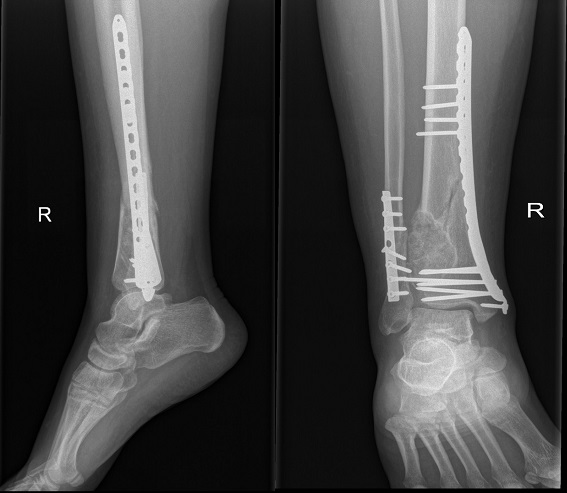

The fracture was first approached via an anterolateral approach to the distal fibula in which the fibula fracture was fixed by a 1/3 tubular plate and screws. This was followed by a complete curettage of the lesion and bone grafting with cancellous bone chips allograft. Finally, the tibia fracture was fixed by minimally invasive percutaneous osteosynthesis (MIPO) technique using 3.5mm locked plate medially (Figure 2). The excised bone material was then sent for histopathological examination which confirmed a non-ossifying fibroma with secondary aneurysmal bone cysts (Figures 3- 5).

Figure 2 Immediate post-operative AP and lateral x-rays - fibula fracture fixed with a 1/3 tubular plate and screws with the lesion curretaged and filled with allograft; and the tibia fixed by MIPO plate and screws.

The patient was initially placed on a non-weight bearing protocol for eight weeks with only crutch and touch-toe ambulation. Follow-ups were carried out at two weeks, four weeks, eight weeks, sixteen weeks, eight months and one year post-operatively. At eight weeks, the ankle range of motion was regained and a healing callous started to form. The patient was, therefore, allowed to partially bear weight. At 4 months post-operatively, full weight bearing was started when the patient had a painless full range of ankle motion and x-rays revealed good incorporation of the allograft (Figure 6). Examination at eight months and 1 year post-operatively revealed full ankle strength and range of motion restoration with a complete filling of the defect and total fracture healing (Figure 7).

Figure 6 AP and lateral x-rays 4 months post-operatively-maintained osteosynthesis and good incorporation of the allograft within the lesion.

Figure 7 AP and lateral x-rays 1 year post-operatively. Complete resolution of the fracture.